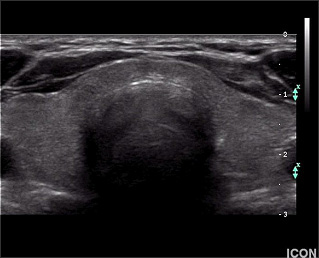

Ακόμα και όταν η βιοψία θυρεοειδούς δείξει καλοήθεια, το μέγεθος του όζου θα πρέπει να παρακολουθείται. Το υπερηχογράφημα παρέχει αντικειμενικό και ακριβή τρόπο ανίχνευσης μεταβολών στο μέγεθος του όζου. Ένας καλοήθης όζος (από τη βιοψία) που παραμένει σταθερός σε μέγεθος ή που φαίνεται να μικραίνει σε διαδοχικά υπερηχογραφήματα, δεν είναι πιθανό να είναι κακοήθης και να απαιτεί χειρουργική αφαίρεση. (Εικόνα Β, Γ).

Εικόνα Β (Φυσιολογικός θυρεοειδής αδένας σε υπερηχογράφημα)

Εικόνα Γ (Συμπαγής όζος στον αριστερό λοβό του θυρεοειδούς σε υπερηχογράφημα)